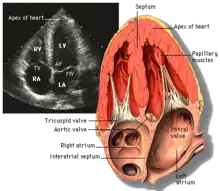

Echocardiography

Echocardiography is regularly utilized to diagnose, manage, and monitor patients with suspected or established heart ailments, making it a highly prevalent diagnostic imaging technique in cardiology due to its speed and efficiency.[3]

Transthoracic echocardiography (TTE)

Transthoracic echocardiography (TTE) uses ultrasonic waves for continuous heart chamber and blood movement visualization. It is the most commonly used imaging tool for diagnosing heart problems, as it allows non-invasive visualization of the heart and the blood flow through the heart, using a technique known as Doppler.

TTE is commonly used to evaluate patients with coronary artery disease.[4] Stress echocardiography is used to diagnose coronary artery disease and assess myocardial viability.[4]